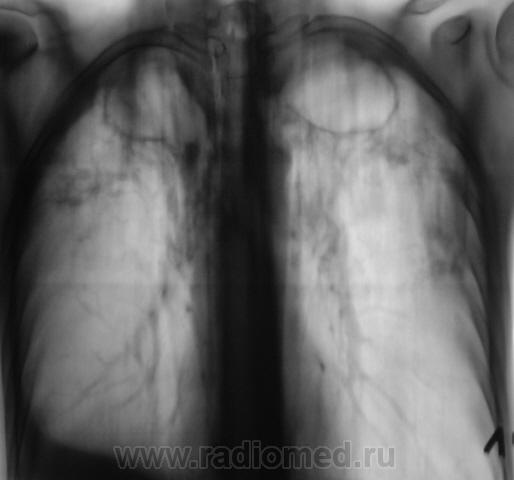

Мужчина, работает в областном центре, "в охране". Приехал проведать маму, так как мама заболела. На 3 день почувствовал себя "не очень" и решил обратиться в местную поликлинику к терапевту. В регистратуре выяснили, что мужчина в течение 3-х лет профилактическую флюорографию не проходил и направили во флюорографический кабинет.

Сразу-же, после производства флюорограммы, пациент был дообследован в рентгенодиагностическом кабинете согласно стандарту.

добрый день. мама как раз может и не болеть.а у ее сына хороший инфильтративный туб-з с распадом и обсеменением,но процесс не "свежий",есть объемное уменьшение в\д справа,нет перикавитарной инфильтрации,но активный. из вновь приобретенной патологии-экссуд.плеврит справа. немного удивляет:б-ой из области,скорее всего "обязательный контингент" ,и рфо более 3лет.иногда из иту приходят с меньшими процессами. в мокроте нашли куб?

1. Я выставил без "всяких" фиброзно-кавернозный. Далее коллеги-фтизиатры разберутся.

Фтизиатры согласились с ФКТ, палки при микроскопии - море.